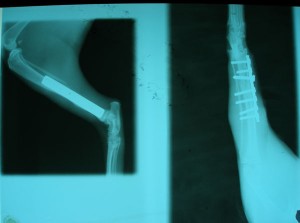

Po operaci obou kostí

Teď nás čeká další rentgen. Pokud bude srůst kostí dostatečný, bude Murri muset přestát ještě operaci, kde mu budou vytaženy šrouby. Předpokládané další náklady tedy budou spojené s dalším rentgenem a operací. Cenu budu zítra opět konzultovat / jdeme na vyšetření a zásah s kocourkem, který má problémy v tlamičce/. Pak budeme nožku v průběhu dalších měsíců pomalu zatěžovat tzn, že Murri bude mít krátké, kontrolované procházky a budeme cvičit. Zatím je stále ve velké kleci, která mu dovoluje dost pohybu a bezpečné zatížení nohy. Na nožku zatím výrazně kulhá, nerad ji zatěžuje, myslím, že mnohé je důsledkem ochablé svaloviny. Podstatný bude rentgen.